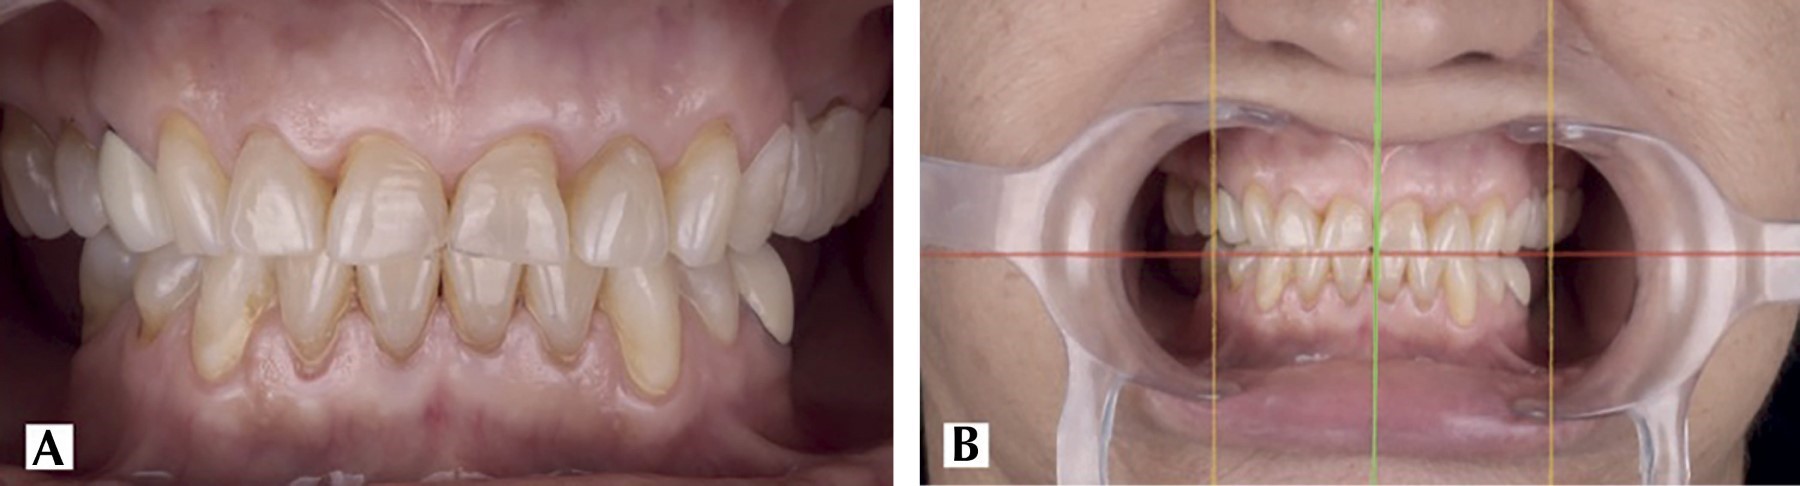

Introduction: the digital flow has reinvented processes in dentistry, from diagnostic methods to surgical protocols. The precision and brevity offered by digitalization has encouraged research and incorporation by the clinic to speed up time and reduce errors in dental treatments. The goal is to introduce even more digital flow in surgical procedures to reduce the operating time for the patient and the operator. Clinical case: a 70-year-old female patient, ASA I, referred by the Prosthodontics Department for crown lengthening in order to achieve compensation of the dentogingival tissues with the occlusal plane correction through the use of crown lengthening previously planned in EXOCAD. Pre and transoperative time was reduced, obtaining a more accurate symmetrical smile and gingival margin without compromising occlusion and periodontal tissues. Computer-aided design and manufacturing broadens the perspectives in a treatment plan, three diagnostic methods such as tomography, intraoral scanning and facial photographs are used together to perform a digital wax-up and articulator.

Figure 1